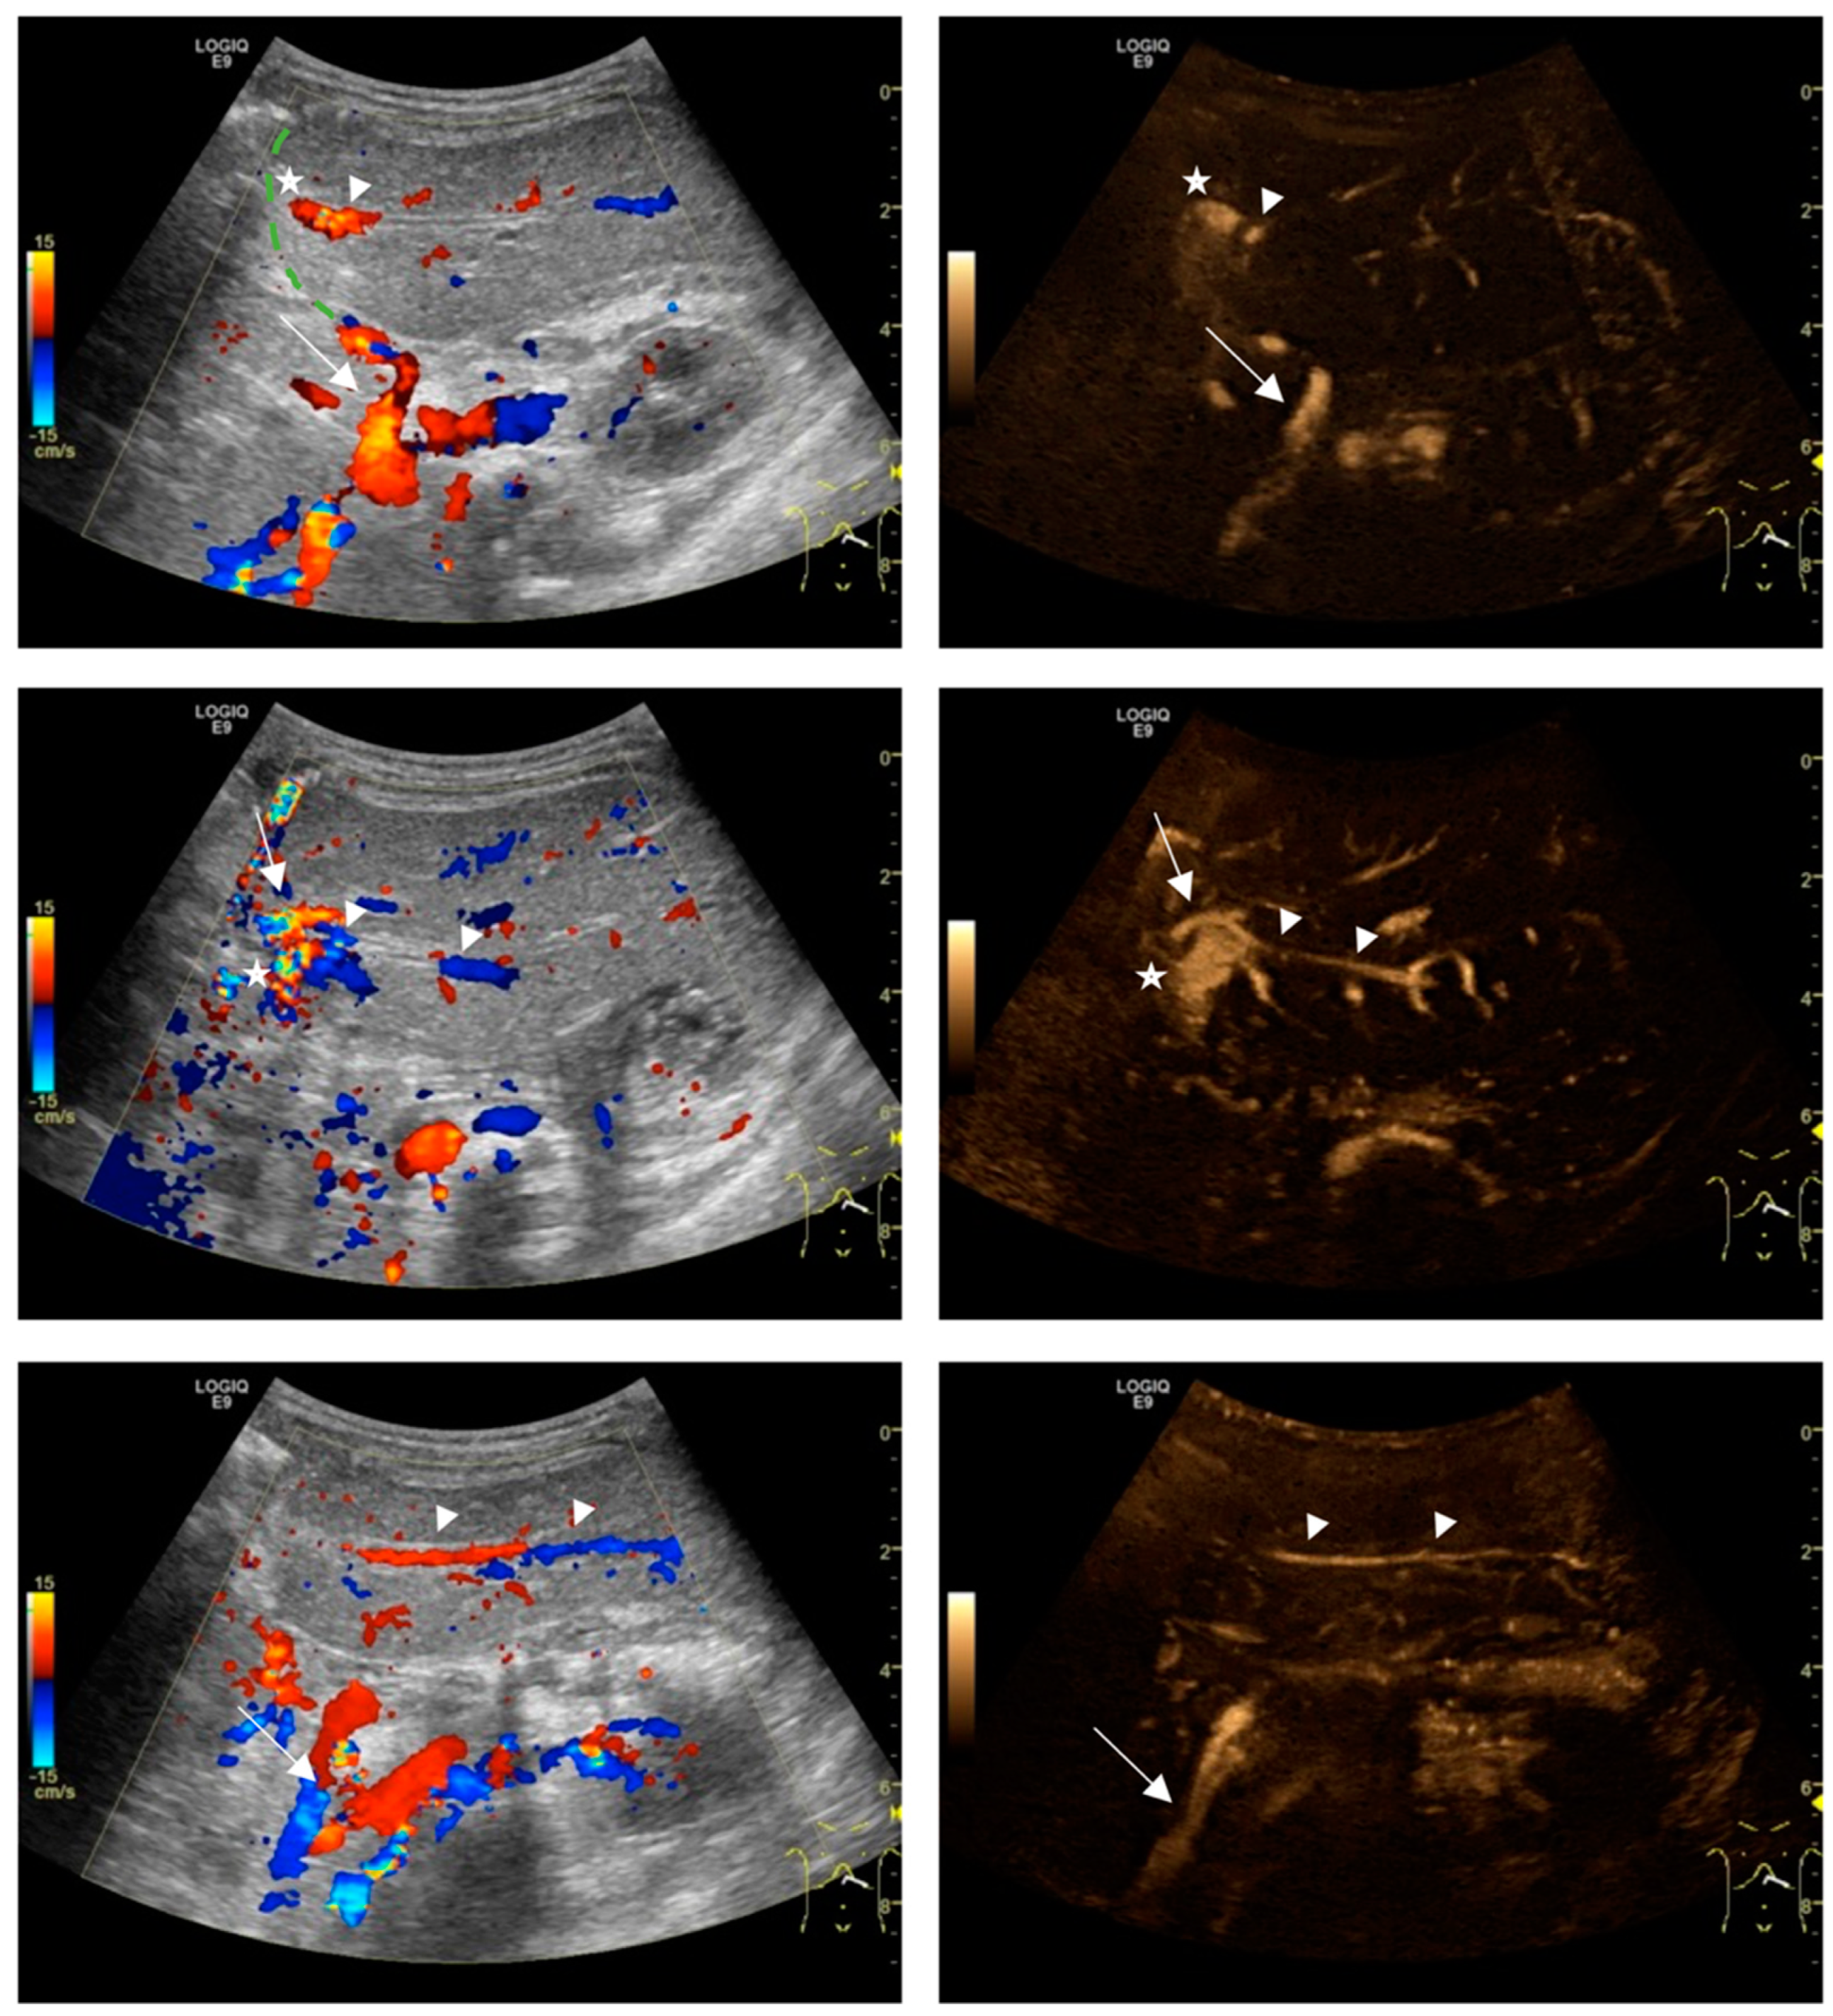

- -

- S 0 = HA not detectable, only PV detectable

- S 1 = HA discontinuously detectable but not separable by a gap from the PV

- S 2 = HA continuously detectable but not separable by a gap from the PVor HA discontinuously detectable but separable by a gap from the PV

- S 3 = HA continuously detectable and completely separable by a gap from the PV